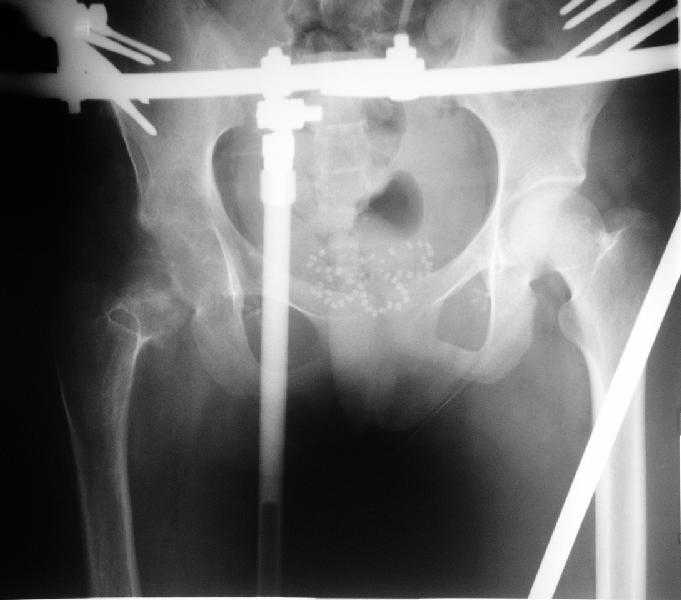

Здравствуйте уважаемые коллеги.Больная 18 лет. Травма 12.08.2007. Лечилась в одном из городов Свердловской области.

15.08.2007 в ЦРБ сделан открытый остеосинтез правого бедра интрамедуллярным стержнем, после чего была наложена гипсовая кокситная повязка и пациентка лечилась амбулаторно в течение 1,5 месяцев. На контрольном Rn исследовании в марте 2008 диагностирован подвздошный вывих правого бедра.

Поступила к нам в отделение. В отделении первым этапом был наложен аппарат внешней фиксации для низведения бедра. 30.09.08 интрамедуллярный стержень удален. Вторым этапом планируется эндопротезирование. В настоящее время у больной имеется контрактура коленного сустава, с амплитудой движений в пределах 30 градусов., и выраженный остеопороз вертлужной впадины и проксимального отдела бедра. Больныя пердвигается самостоятельно с опорой на здоровую ногу и костыли.